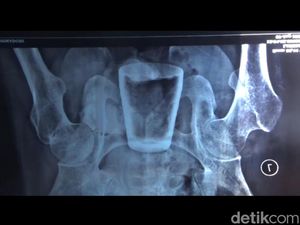

Gelas di dalam perut warga Jember, sudah dikeluarkan melalui operasi. Namun banyak warga yang masih mempercayai peristiwa tersebut gara-gara santet.